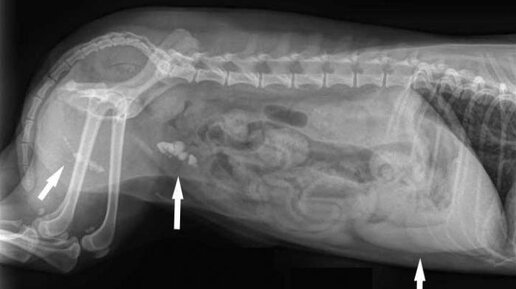

Мочекаменная болезнь у котов (МКБ) вызвана нарушением обмена веществ, при котором в мочевыводящих путях образуются песок или камни. Серьезные отклонения требуют своевременной коррекции, так как это небезопасно для жизни животного. Виды камней и их природа при развитии мочекаменной болезни у котов При МКБ в органах выделительной системы кошек формируются твердые минеральные отложения — мелкий песок и более крупные камни (известны также как уролиты или конкременты). Они бывают двух типов, отличающихся химическим составом и структурой: Струвиты — более распространенный вид камней в почках у котов...

Мочекаменная болезнь (уролитиаз) у котов одна из самых распространенных недугов. Иногда она встречается и у кошек. Эта болезнь  характеризуется нарушением обмена веществ у животного, которое сопровождается отложением и образованием камней в почках, уретре и мочевом пузыре. Чаще всего уролитиазом болеют коты от 1 до 6 лет, 70% из которых имеют избыточный вес. Наиболее подвержены мочекаменной болезни домашние длинношерстные и персидские кошки. Часто уролитиаз обостряется у котов с января по май или с сентября по декабрь...